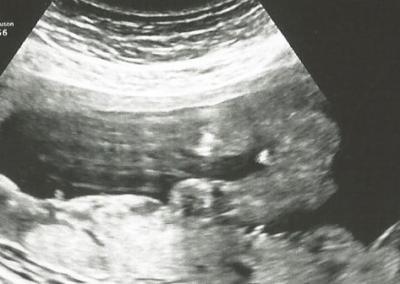

was gibt es denn bei so einem Bild wie meinem damals ein restrisiko???? also manchmal ist die floskel echt weit hergeholt

Bild zu

Auf Deinen Bild sehe ich jetzt ehrlich gesagt nicht so viel, aber wenn sich der FA so festlegt wird das stimmen. Ich habe ibei mir n der 16. SSW mit eigenen Augen gesehen, dass es ein Junge wird.